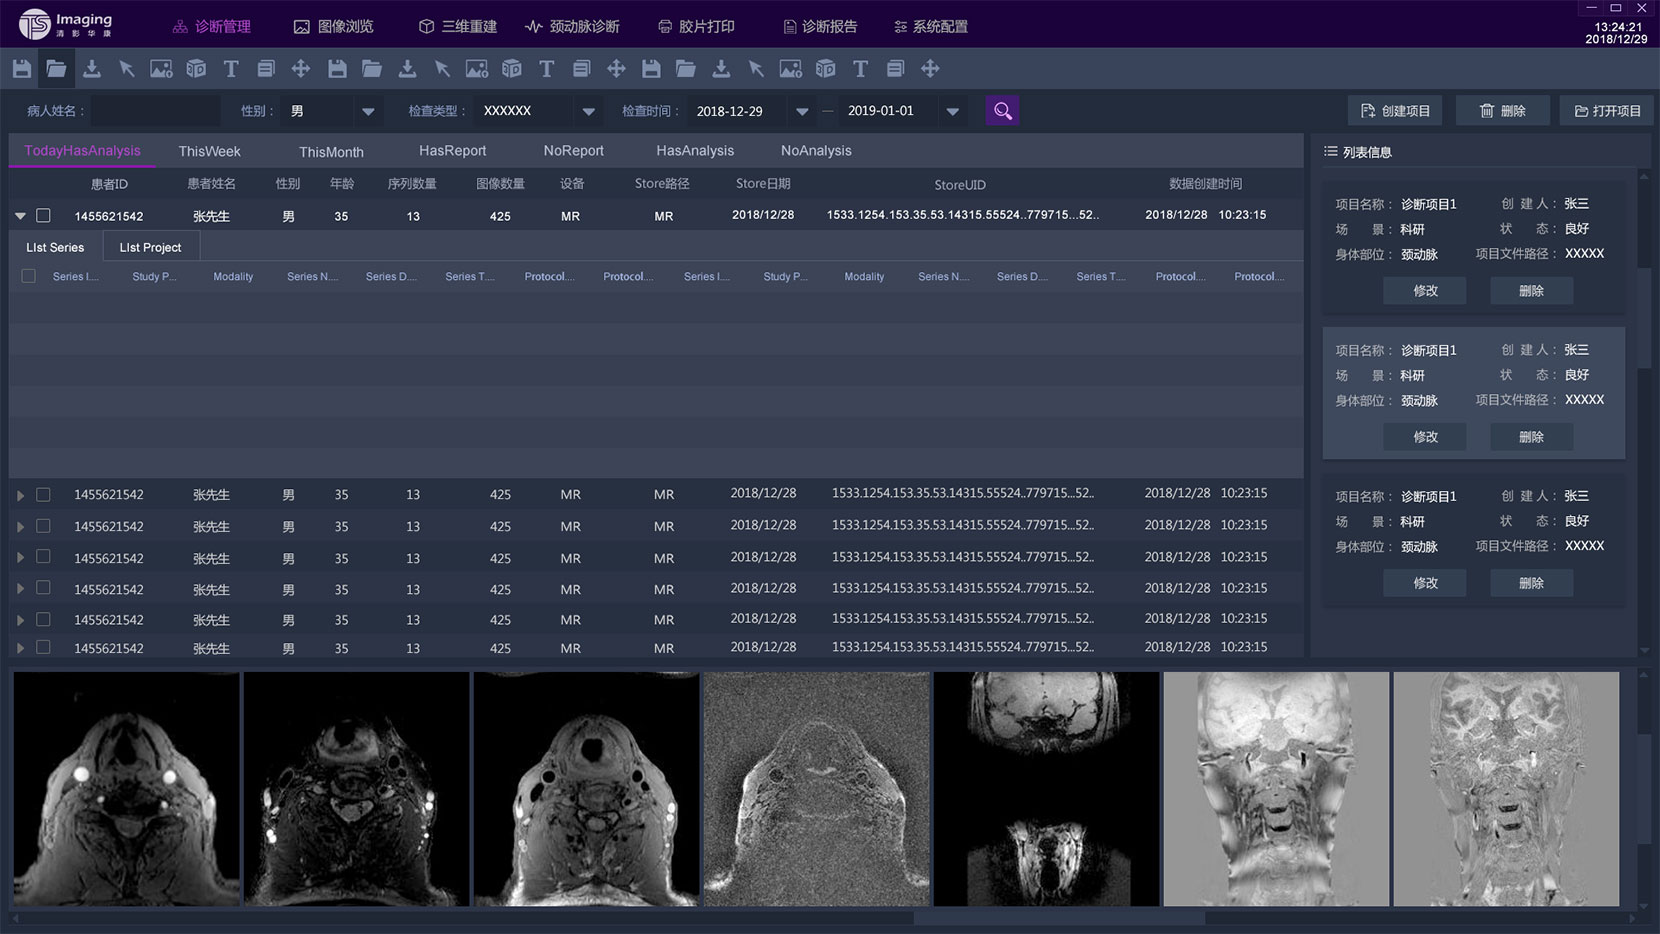

診斷管理頁面

診斷管理頁面相對其他頁來說交互關系比較復雜,表單里面還套了一個子表,為了更好的區分兩者,tab的形式、底色和字體大小等等做了明顯的區分。這部份也是在設計過程中調的較多的地方。左側是一個信息列表的展示,通過下方的按鈕也可進行操作。下方是影像的縮略圖,點擊之后可放大。

這是雙方首次溝通后出的兩個方案,方案以深灰為主,考慮到該軟件是醫療圖像處理軟件,以深灰為主可以突出要操作的信息,同時上時間操作不會刺眼,緩解視覺壓力。方案二是在方案一的基礎上做了色彩搭配的的調整,為了使整體的色調和

公司logo的顏色更加協調統一。

客戶反饋這兩方案比較普通,想頁面有科技感一點,同時也給我們提供一些他們認為比較好的設計,我們雙方再次討論后出的第三套方案,客戶也比較認同。